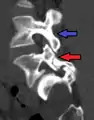

Anterolisthesis L5/S1

Anterolisthesis L5/S1. Blue arrow normal pars interarticularis. Red arrow is a break in pars interarticularis